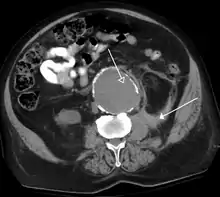

FIGURE 3. Axial (left) and coronal (right) CT angiography images of the abdominal aorta evaluating for aortic aneurysm.

CT angiography (CTA) is highly effective for evaluation of the arterial system, and has largely replaced conventional angiography due to the lower risk profile and ability to survey the entire abdomen. Images are acquired after a rapid bolus of intravenous contrast material (3-7 cc/s) during the arterial phase (15–35 seconds after injection) when the concentration of contrast material in the arterial system is high (figures 3). Images are usually acquired using narrow collimation (<1 mm) and can be retrospectively reconstructed using dedicated 3-dimensional workstations and software. CTA is commonly used in the head and chest in the evaluation of pulmonary emboli, aneurysms, vascular malformations, dissection, bleeding and ischemia. Indications for early arterial phase imaging include: evaluation of aneurysms or dissections (cerebral, aortic, etc.), hepatic, splanchnic or renal arterial anatomy, and arterial imaging in liver or kidney transplantation. Single phase arterial imaging is often used in the evaluation of trauma patients either a complete chest/abdomen/pelvis examination with arterial phase imaging of the chest and portal venous phase imaging of the abdomen/pelvis or just a portal venous phase of abdomen and pelvis depending on the mechanism and severity of the trauma. CTA is also commonly performed in the abdomen and pelvis for evaluating vascular malformations and in the evaluation of bleeding. Mesenteric ischemia can also be evaluated using CT angiography. CTA of the abdomen and pelvis is often performed in combination with a CTA for evaluating the extremity vasculature.